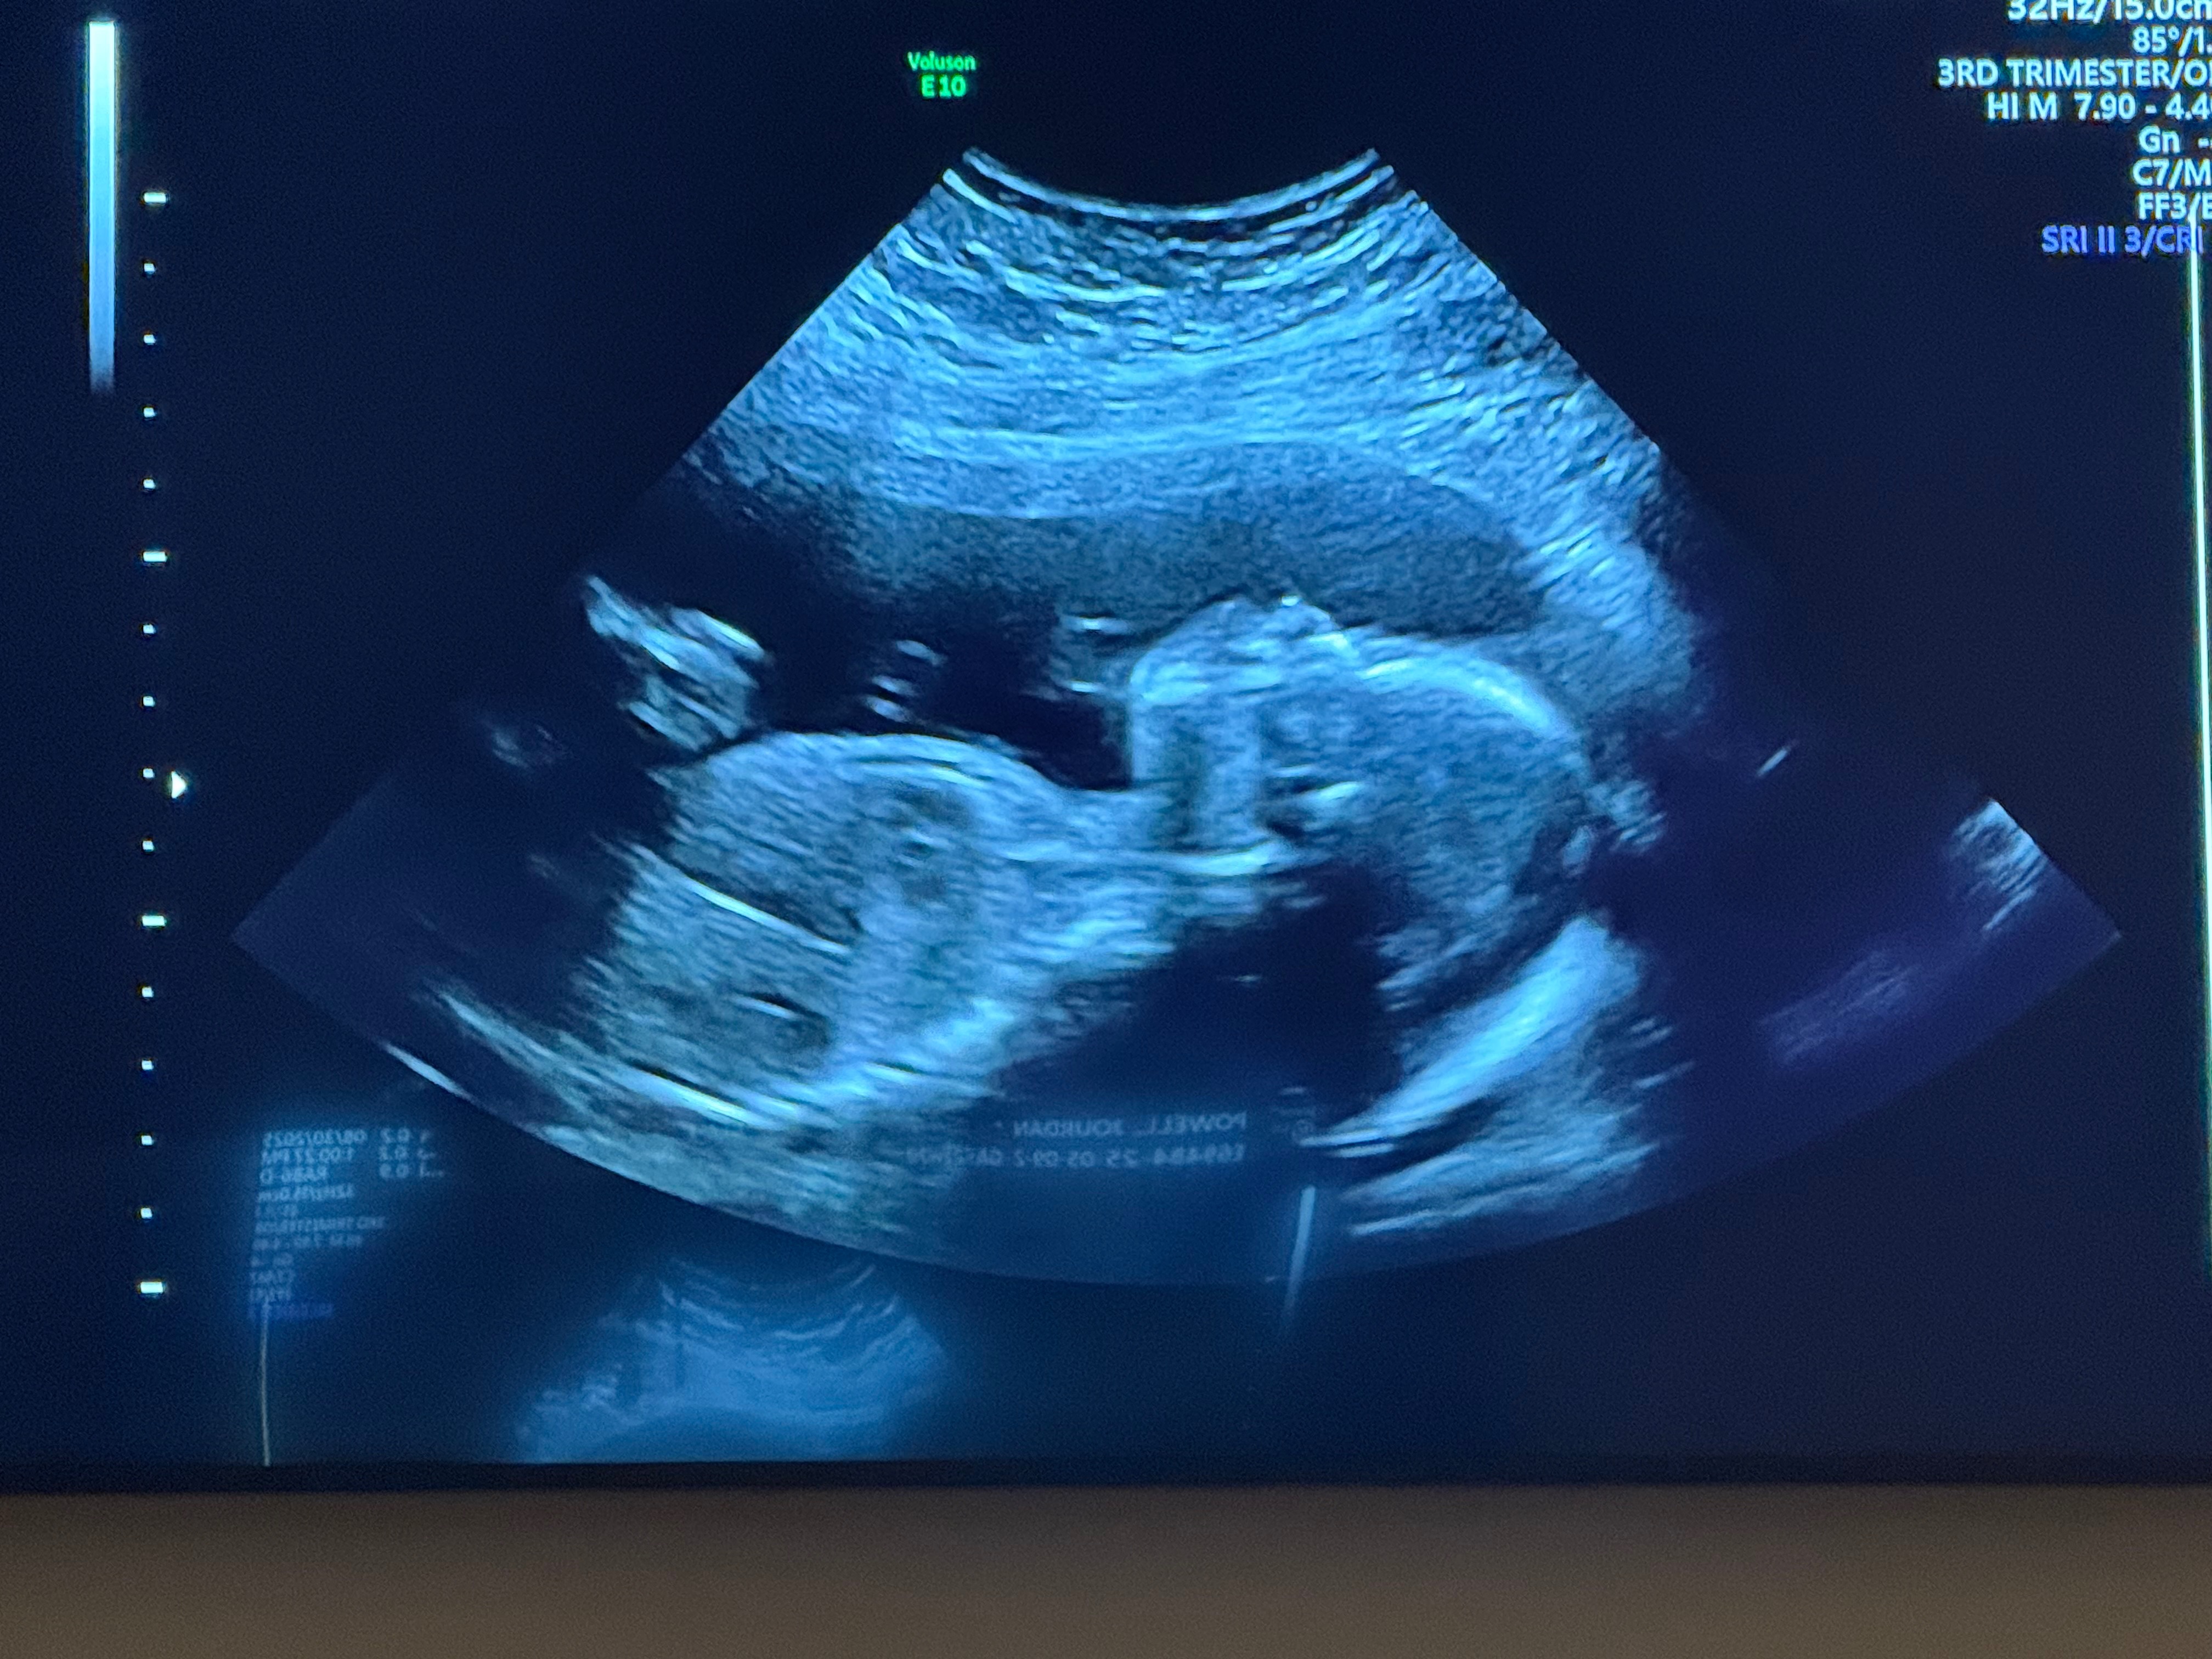

Jourdan was hospitalized on Thursday with complications as her blood pressure was dangerously high. She has been diagnosed with pre-eclampsia, and due to a headache that won’t go away, she was transferred to Barnes-Jewish in St. Louis. On 11/02, she will have an MRI to try to determine the cause of the headaches. Please pray for peace and comfort. We are trusting God will bring us to the other side of this safely as He has done so many times before.

Hosanna was originally due Dec. 31, but due to the high-risk pregnancy, they felt they would induce around Dec. 10. Jourdan works part-time and will now remain in the hospital until she gives birth. Chris has no more PTO this year and gets 3 days off (unpaid) for the birth.